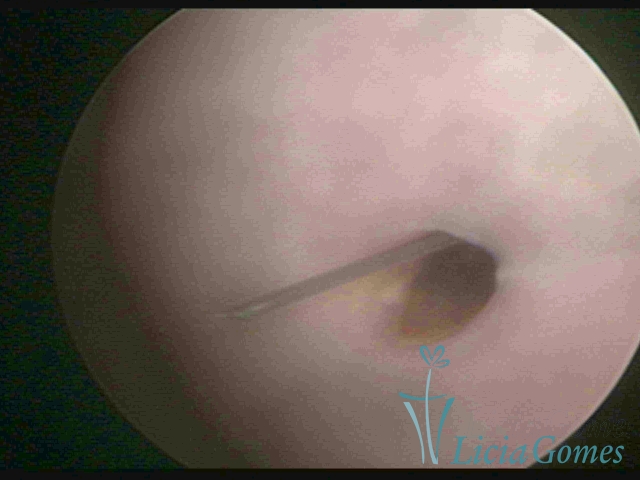

Canal cervical trófico, com o fio de Mirena®